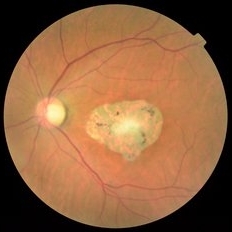

Active Neovascular AMD With Disciform Scar

Apr 30 2015 by Mitzy E Torres Soriano, MD

Active neovascular AMD with disciform scar.

Photographer: Mitzy E. Torres Soriano, MD; Centro medico Cagua-Estado Aragua. Venezuela

Imaging device: TOPCON

Condition/keywords: disciform scar, disciform with hemorrhage, neovascular age-related macular degeneration (AMD), wet age-related macular degeneration (wet AMD)